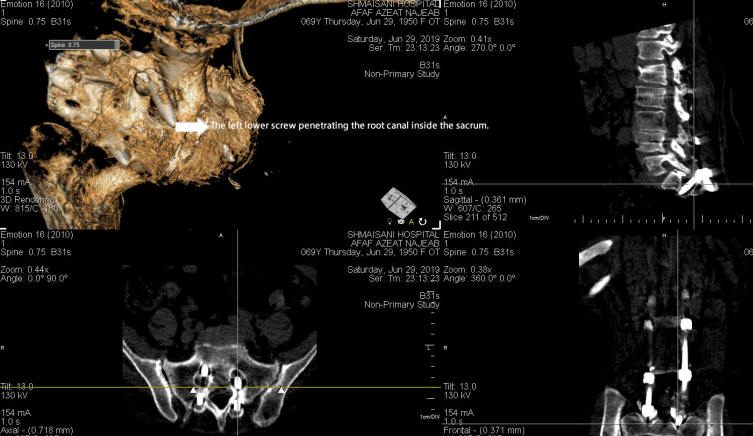

04-JULY-2019  AFAF IZZAT MAJEED  68 YEARS RESIDUAL AFTER FIXATION OF L1 DOWN TO S1 WITH LOWER SCREWS PENETRATING THE S1 ROOTS BOTH SIDES.

The patient was sent for investigations: MRI lumbar spine performed 29-June-2019 ruled out presence of new pathologies above and below the construct. Dynamic studies ruled out overmobility. Lab investigations were uneventful. Ct-scan showed the lower screws penetrating the neural canal both sides inside the sacrum with decompressive laminectomy of L2-3-4. The right L4 root penetrating the intradural space, but the patient is complaining of agonizing left sciatica, for what this finding was ignored. The patient was advised for surgery and start immediately Zinnat 500 twice daily to decrease the possibility of postoperative infection and to be seen by cardiologist.

FIGURE-1 Demonstrating the left lower screw inside the root canal.